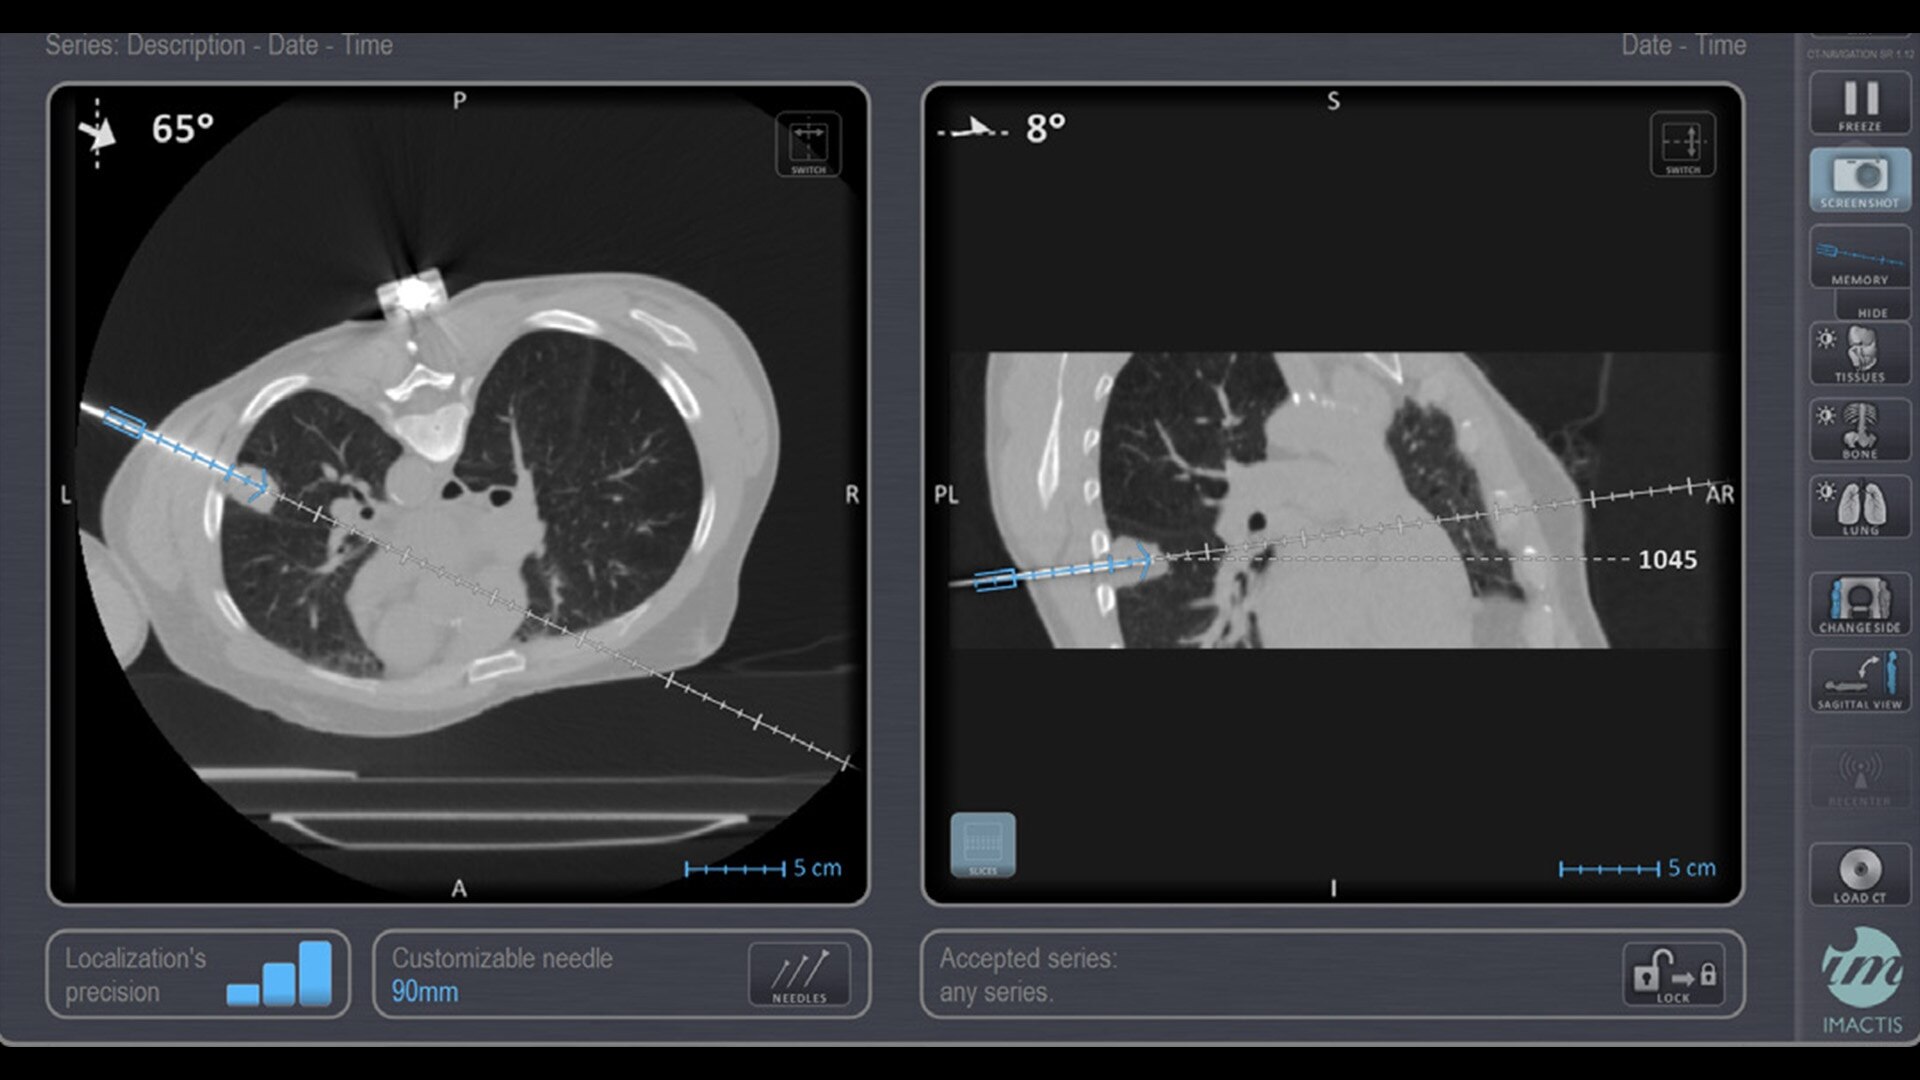

In interventional radiology, the success of the percutaneous procedure depends on correct needle positioning. The Imactis system helps the radiologist place one or more needles with great accuracy, in less time and with fewer control scans.

With real-time image reconstruction, live interactive navigation and no limit in angulation, the optimal clinical choices are clear.

Live 3D needle tracking, precise reproduction of your planned trajectory and continuous needle depth measurement help ensure optimal needle placement.